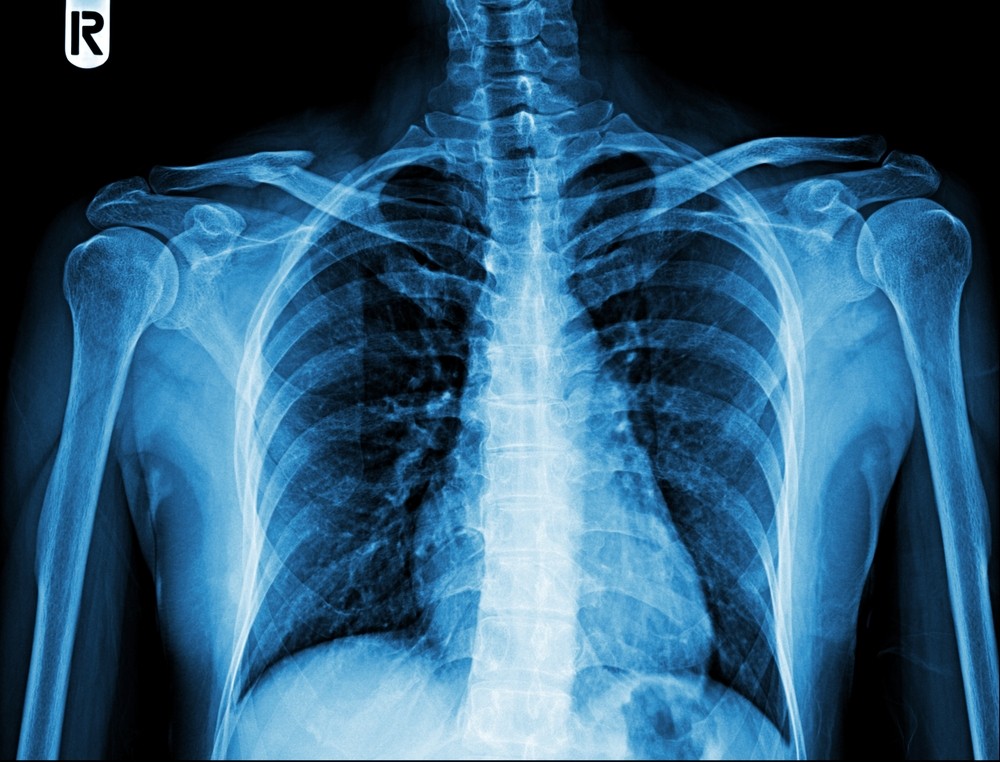

Расшифровка результатов

После рентгенографии лопатки начинается анализ готовых результатов. Врач просматривает изображения. Сравнивает значения с нормой. В своем протоколе специалист указывает характеристики костей, суставных сочленений, соседних элементов. Он отражает выявленные патологии. Пишет выводы.

В норме на рентгене:

- форма лопатки обычная, расположение типичное;

- структура и контуры костей без изменений;

- травмы и деструктивные процессы не определяются;

- опухоли и воспаления отсутствуют.

Полученный отчет и рентгенограммы следует передать лечащему доктору. Врач поставит диагноз. Он расскажет о необходимом лечении. Огласит прогноз.